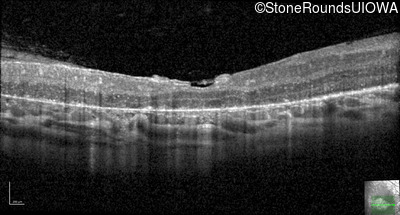

Optical Coherence Tomography - Left - 20/80 -1

Exemplar / OCT Stack